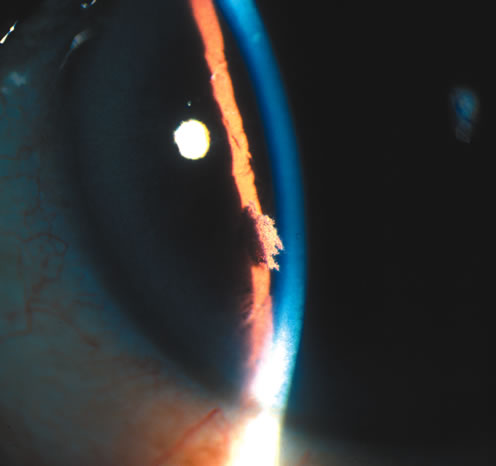

One of the more common reasons for focal iris atrophy in recent years is found in eyes that have undergone extracapsular cataract extraction with placement of an intraocular lens implant.45,47 This is an erosion phenomenon that occurs with anterior chamber lens and sulcus fixated lens (Fig. 7).48,49 Iris atrophy is also seen commonly around surgical or laser iridectomies.

Fig. 7. Iris atrophy with transillumination defects (arrow) after extracapsular cataract surgery with a sulcus fixated intraocular lens. (© University of Illinois at Chicago.)